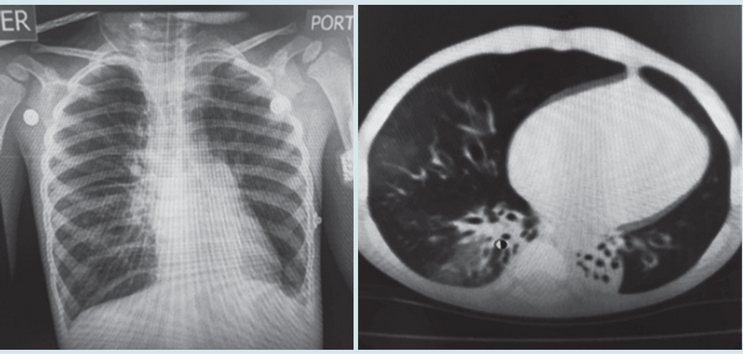

En las Figuras 1 y 2 se observan imágenes diagnósticas de algunos de nuestros pacientes y en la Figura 3 la evolución favorable de la tomografía (en un caso) después de varios años de seguimiento. En nueve casos se realizó exploración funcional respiratoria encontrando obstrucción significativa de la vía aérea en seis, obstrucción leve en dos y ausencia de obstrucción en uno; en 3/8 pacientes se observó reversibilidad del volumen espiratorio forzado en el primer segundo (VEF1). Se hizo seguimiento de la función pulmonar en cuatro pacientes observándose deterioro de la misma en tres (Figura 4). En cuanto a la presión pulmonar se encontró inicialmente elevada en el 43% de los casos, observándose en su seguimiento, disminución en cinco y aumento en uno.

Con relación a las imágenes diagnósticas, todos los pacientes tenían patrón de mosaico en la tomografía de tórax, pues era un criterio de inclusión. Encontramos bronquiectasias en el 33% de los casos, hallazgo frecuente en la bronquiolitis obliterante post-infecciosa reportándose en el 60% de los casos en Fortaleza (Brasil),2 en el 36% en el País Vasco (España) 10 y en el 32% en Porto Alegre (Brasil).4 La identificación de las bronquiectasias es importante pues implica la implementación de medidas terapéuticas como la administración de antibióticos y la realización de terapia respiratoria.

En los casos en que se hizo tomografía de control, con un rango de tiempo entre los dos estudios de 31 a 80 meses, observamos mejoría en las imágenes en 6/8 pacientes. No encontramos en la literatura datos sobre seguimiento de imágenes en bronquiolitis obliterante post-infecciosa que nos permitan hacer una comparación al respecto.